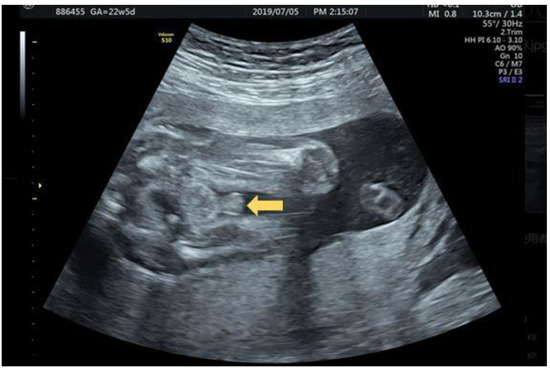

2.4. Case 4